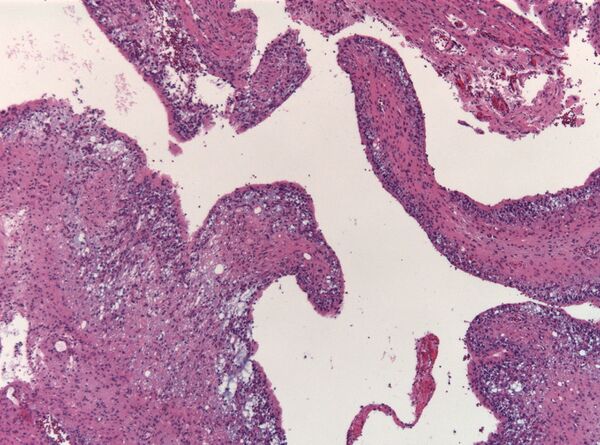

Микропрепарат истинной эпендимомы. На изображении видны как истинные, так и псевдорозетки

1. Основным гистологическим типом является истинная эпендимома , для которой типично наличие периваскулярных и истинных «розеток». Периваскулярные «розетки» («псевдорозетки», «лучистая корона») состоят из клеток новообразования, которые располагаются вокруг кровеносных сосудов. В истинных «розетках» опухолевые клетки находятся вокруг каналов, которые выстланы эпендимарными клетками.